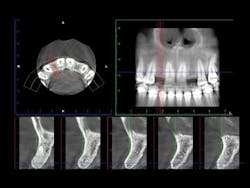

12. The lab will make the guide and send it to you (figures 1 and 2).

Figures 1 and 2:

The lab has made a printed surgical guide for a specific case. The designated drill is easily related to the guide and provides near-perfect placement of the implant.

Figures 4-7: This series of images shows a clinical situation, the cone beam images, and the freehand implant placement.